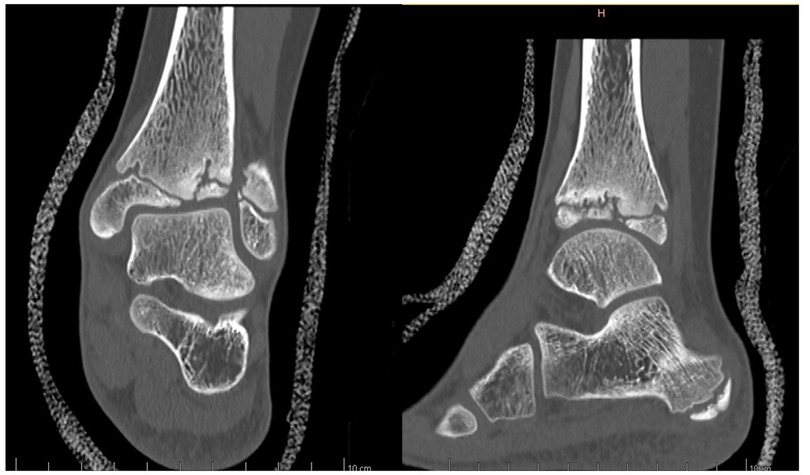

Anamnesis showed no family history of illness, genetic disorders, or osteochondrosis. The patient was 148 cm tall and weighed 37.5 kg, both measurements being one standard deviation above the mean. Clinical exam showed unrestricted, and symmetrical motion in the left ankle. There was a 13 mm leg length discrepancy on the left, and a standing hindfoot valgus angle of 10°. Palpation triggered pain in the joint's anterolateral aspect. Pain was noted over the anterior talofibular ligament with palpation, tension, weight-bearing, and tiptoe walking. The initial x-ray image of the left ankle revealed an irregularity of the distal tibia, with thinning or even an absence of the lateral epiphysis. The physis itself appeared scalloped and was difficult to clearly distinguish on its lateral side. A standing x-ray image of both ankles was taken, and radiographic alignment analysis revealed valgus of the joint line of the left ankle, with a mechanical distal lateral tibial angle measured at 76° (Figure 1). Unexpectedly, we identified trophic disturbances in the distal epiphysis of the contralateral tibia, indicating the presence of bilateral osteochondrosis. Indeed, the right epiphysis appeared to be both atrophic and sclerotic, but without fragmentation. A CT scan confirmed the fragmentation of the left epiphysis and a complete disruption of the physis on its lateral side. In certain instances, the imaging findings were indicative of possible physeal bars (Figure 2). MRI also confirmed the fragmentation and subsequent involution of the distal tibial epiphysis. It also revealed severe focal alterations in the physis and important metaphyseal deformities consecutive to abnormal endochondral ossification, as well as serious structural alterations in the articular cartilage (Figure 3). No lateral ligamentous or syndesmotic instability, nor rupture, was evident. A diagnosis of bilateral osteochondrosis of the distal tibial epiphysis was made, and the patient was prescribed a symptomatic treatment involving a prohibition of any sports activities and temporary immobilization in a left plaster cast for four weeks without weightbearing due to pain.

Figure 2. This CT scan of the left ankle more precisely revealed the extent of the damage to both the epiphysis and the physis, demonstrating epiphyseal fragmentation with physeal disruption and the presence of physeal bars.